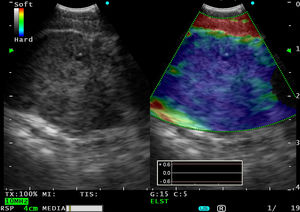

Varón de 74años, fumador, con hipertensión arterial, dislipidemia, infarto agudo de miocardio antiguo y poliglobulia. Refería cuadro de disfonía progresiva desde hacía mes y medio y cuadro de inestabilidad desde hacía 3-4meses, pero que en los últimos días se había intensificado hasta impedir la bipedestación. En la TAC torácica se observó un nódulo pulmonar de 2cm en el lóbulo superior derecho, sugestivo de neoformación pulmonar primaria, múltiples pequeños nódulos pulmonares bilaterales sugestivos de metástasis y múltiples adenopatías mediastínicas aumentadas de tamaño. Se realizó una TAC craneal, en la que se apreciaron signos radiológicos compatibles con múltiples metástasis cerebrales. Con el ecobroncoscopio (bajo sedación consciente [midazolam]) se accedió por vía esofágica, dada la existencia de importante edema cerebral6, y se visualizó una adenopatía subcarinal de 20mm que se puncionó. El modo elastografía indicaba que la consistencia estaba marcadamente aumentada (fig. 2). El diagnóstico fue metástasis de adenocarcinoma de pulmón.